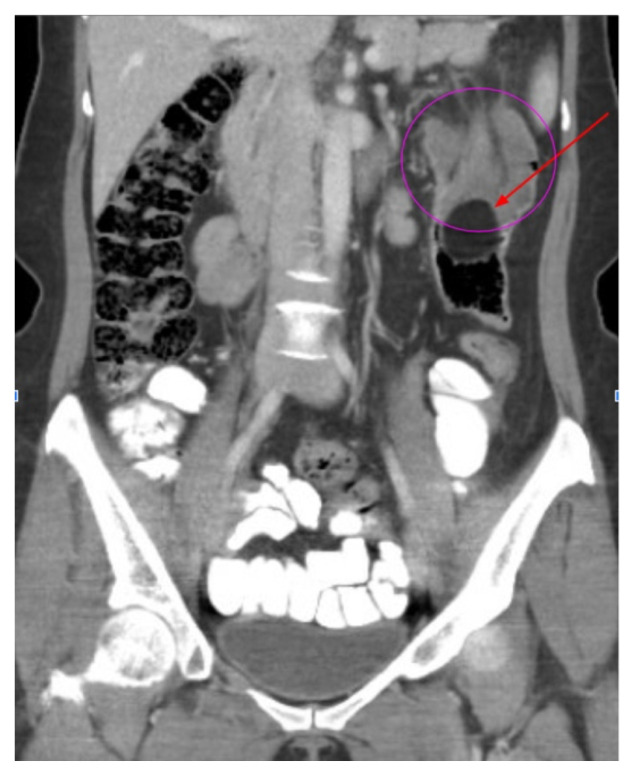

Intussusception is a familiar diagnosis among the pediatric population; however, it is rarely considered among the adult population due to a myriad of life-threatening pathologies within the abdomen. We present an adult female who presented to the emergency department (ED) with abdominal pain and constipation. Laboratory testing and a computed tomography (CT) scan of the abdomen were ordered. Laboratory test results were notable for an elevated lymphocyte count as well as leukocyte esterase, white blood cells (WBC), and bacteria seen on urinalysis. The computed tomography scan detected a colo-colic intussusception secondary to a benign mass within the bowel lumen. The mass was surgically resected and the patient had an uneventful postoperative course. This unique case represents the occurrence of a pathology to which the adult population is not immune, and therefore should not be overlooked when evaluating a non-specific case of abdominal pain.

Topics: Intussusception, colo-colic, obstruction, abdominal pain, constipation, female, mass, bowel, lymphocyte, ultrasound, computed tomography.